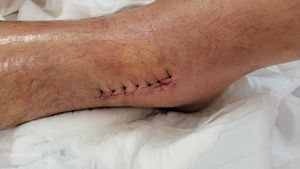

Olá,  sofri um acidente e quebrei o meu tornozelo, coloquei 9 parafusos e uma placa de aço cirúrgico no Hospital de Taguatinga (HRT).

Sou vidraceiro profissional a 22 anos e neste momento estou em casa sem poder exercer o que mais gosto que é a minha profissão, sou o provedor da minha casa e passarei por uns 6 meses de recuperação e com essa vaquinha busco conseguir o sustento até então destes longos dias que ficarei de repouso em casa.